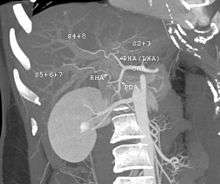

- Before one becomes a living donor, the donor must undergo testing to ensure that the individual is physically fit. Sometimes CT scans or MRIs are done to image the liver. In most cases, the work up is done in 2–3 weeks.[10]